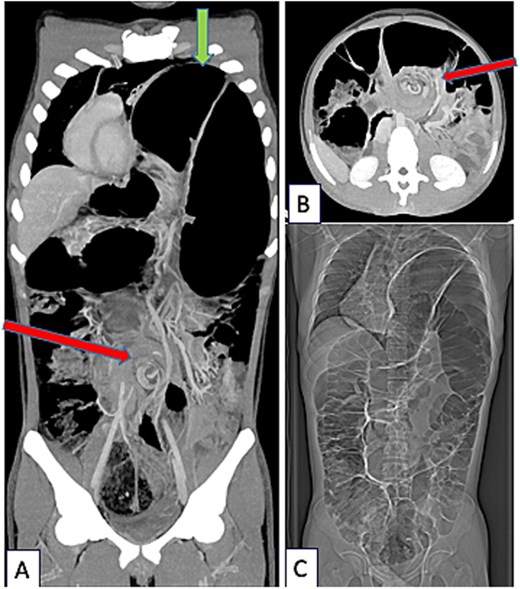

An 18-year-old male originally from Egypt presented to the emergency department with severe abdominal pain suggestive of bowel obstruction. Over the preceding 10 days, he had experienced recurrent non-bilious vomiting, and bowel movements had ceased for 48 h. Since childhood, he had suffered from frequent constipation and had developed chronic abdominal pain during the past year. He had never engaged in sports, particularly endurance activities, and had taken no chronic medication other than laxatives. Physical examination revealed a markedly distended abdomen and absence of breath sounds on the left side. Contrast-enhanced chest and abdominal computed tomography (CT) demonstrated a mesentero-axial sigmoid volvulus with a characteristic “whirl sign,” without evidence of perforation (Fig. 1A and B). The most distended segment of colon had migrated into a large left diaphragmatic eventration, causing mediastinal shift and complete left lung atelectasis (Figs 1C and 2A). Laboratory tests showed no inflammatory response. Under general anesthesia, an initial bedside endoscopic decompression achieved partial detorsion, requiring a second successful endoscopic procedure. Owing to the presence of megacolon and marked mesenteric laxity, the risk ofrecurrence remained high, and surgical management was indicated. Due to organizational constraints, a two-step surgical strategy was adopted. First, an open sigmoidectomy with mechanical end-to-endcolorectal anastomosis was performed. Before thoracic correction, dynamic thoracic magnetic resonance imaging confirmed persistent massive eventration (Fig. 3A), with major mediastinal displacement and absence of contractile activity of the left hemidiaphragm. Pulmonary function tests showed an forced expiratory volume in one second at 71% of predicted (decreasing to 64% in the supine position) and a vital capacity of 74%. Two months later, diaphragm plication reinforced with prosthetic mesh was performed through a video-assisted lower lateral mini-thoracotomy. Intraoperative findings confirmed a massive eventration leaving minimal space for the compressed left lung (Fig. 3B). The diaphragm was extremely thin—~1 to 2 mm—appearing nearly transparent after incision (Fig. 3C). Postoperative recovery was uneventful, except for a transient functional bowel obstruction managed medically. Histopathologic examination of the resected colon ruled out Hirschsprung disease and revealed chronic ischemic changes with fibrosis separating the external muscular layer (Fig. 3D). Four months after the final procedure, the patient showed clear clinical improvement, with normalized bowel habits and the ability to climb several flights of stairs without dyspnea. Chest X-ray confirmed left lung re-expansion and mediastinal repositioning (Fig. 2B). Chronic colonic distension persisted without symptoms and exerted mild upward pressure on the repaired left hemidiaphragm.

CT-scanner thoracic abdominal and pelvic at portal phase (Siemens X-Cite 2021 Healthcare Erlangen Iomeron 350), coronal (A) and axial view (B). Sigmoid Volvulus with pathognomonic Whirl Sign (arrow in the middle of figures A and B) associated with severe diaphragmatic eventration (arrow at the top of figure A). Complete coronal view (C): global colonic distention.